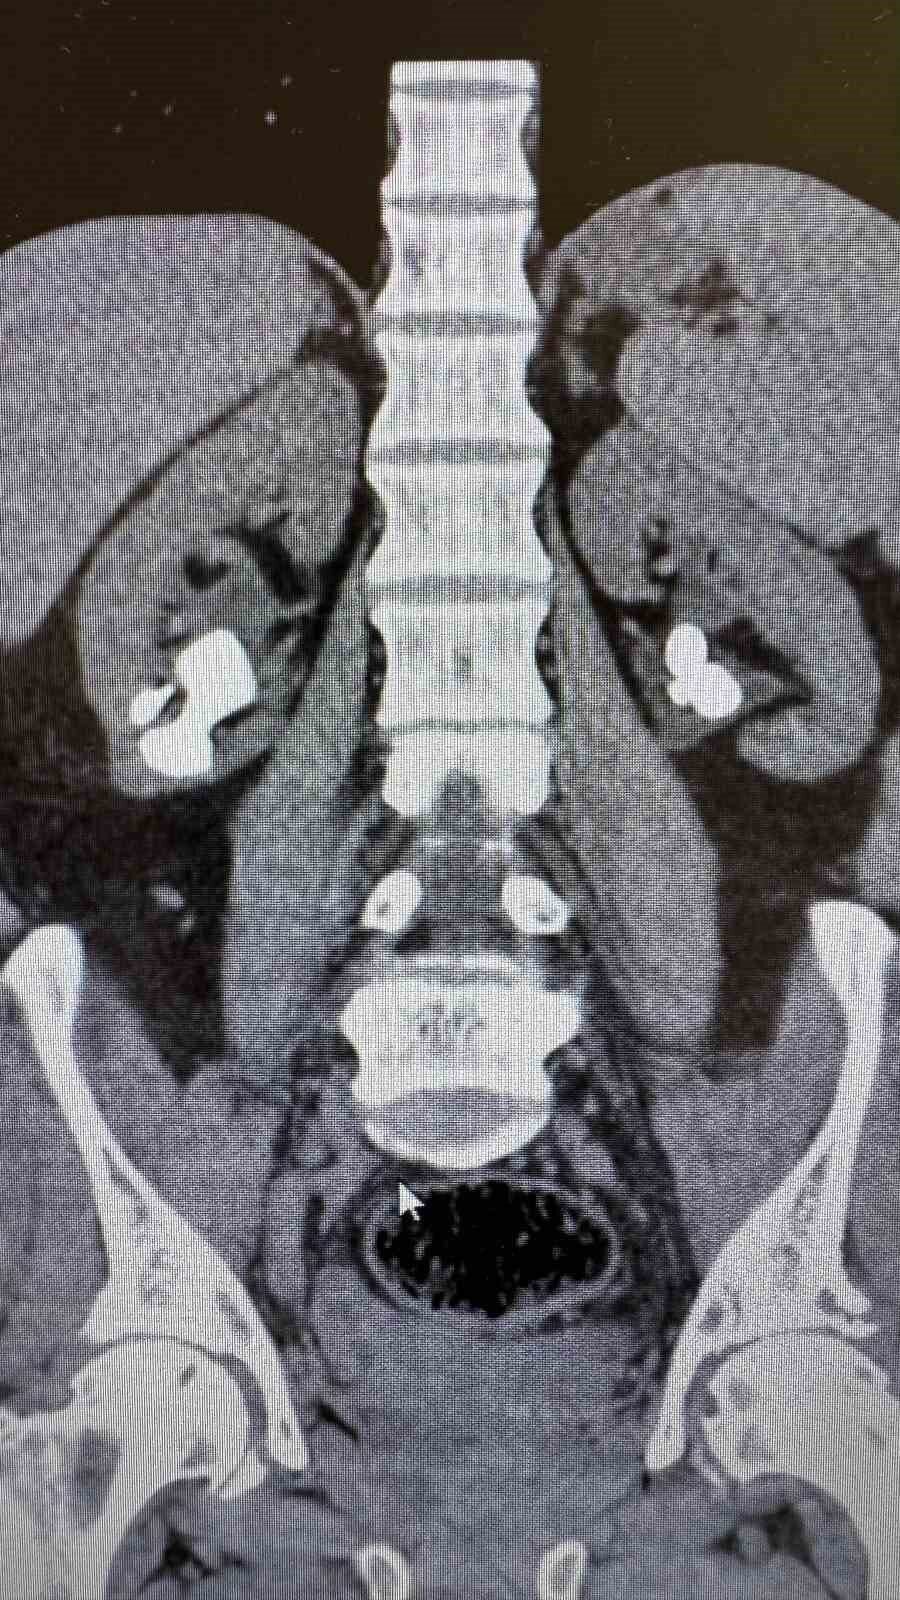

Antalya Gazipaşa Devlet Hastanesi’nde gerçekleştirilen iki başarılı operasyonla 62 yaşındaki hasta böbrek taşlarından tamamen kurtuldu.

Üroloji Uzmanı Op. Dr. İlker Fatih Şahiner ve ekibince kapalı yöntemle (PNL) yapılan ameliyatlarda hastanın her iki böbreğindeki tekrarlayan sistin taşları temizlendi. Hastanın daha önce 10’un üzerinde böbrek taşı ameliyatı geçirdiği öğrenildi. Mayıs ayında yapılan ilk operasyonla sol böbrekteki taşlar alınırken, geçtiğimiz salı günü gerçekleştirilen ikinci operasyonla sağ böbrekteki taşlar da temizlendi.

Operasyonları gerçekleştiren Üroloji Uzmanı Op. Dr. İlker Fatih Şahiner, “Hastamızın her iki böbreğinde de tekrarlayan sistin taşları mevcuttu. Mayıs ayında sol böbreğine PNL yaparak taşsızlık sağlamıştık. Dün de sağ böbreğine PNL ameliyatını yaparak taşsızlık sağladık. Hastamızın genel durumu iyi, tedavisi servisimizde devam ediyor” dedi.